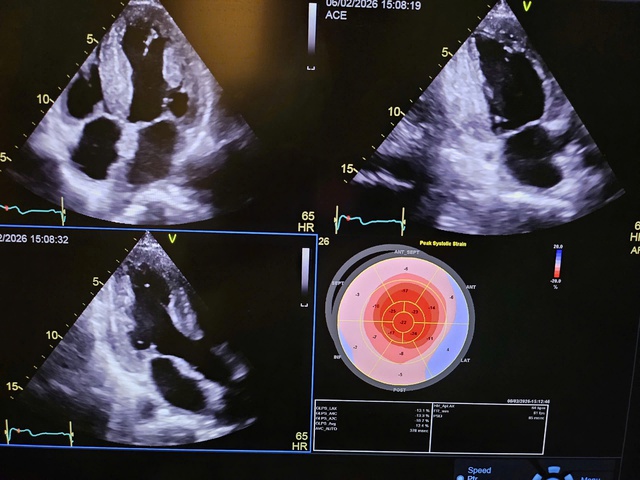

Để đánh giá kỹ lưỡng hơn, bệnh nhân được chỉ định thực hiện thêm các đánh giá lâm sàng và chẩn đoán hình ảnh bao gồm siêu âm tim. Bệnh nhân được phát hiện có phì đại cơ tim, nghi ngờ amyloidosis (thoái hóa dạng bột) – một bệnh lý hiếm gặp liên quan đến cả tim và hệ thần kinh. Khám thần kinh cho thấy bệnh nhân có các dấu hiệu gợi ý bệnh lý thần kinh ngoại biên, có thể giải thích tình trạng yếu vận động.

Đến đầu năm 2026, tình trạng thâm nhiễm cơ tim đã gây suy tim tiến triển, chức năng tim giảm nhanh chóng so với lần thăm khám trước, trong khi các vấn đề thần kinh vẫn ổn định. Bác sĩ Sabrina, bác sĩ Thủy và các bác sĩ Bệnh viện Hữu Nghị Việt Đức thống nhất nhận định, để điều trị triệt để, cần phải thực hiện ghép đồng thời cả tim và gan.